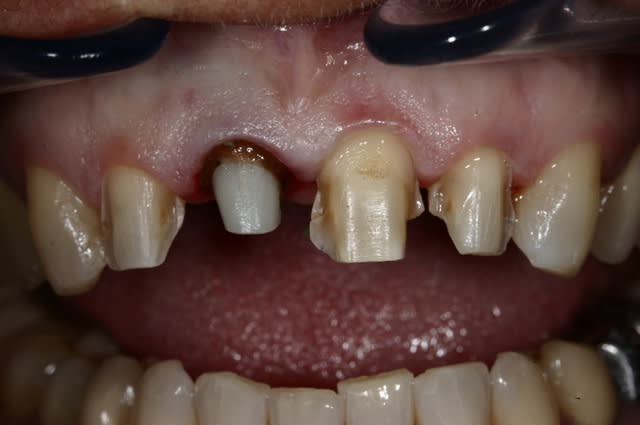

Tout est dans le titre....dans certains cas, malgré mes efforts, il arrive qu'il persiste un aspect legèrement bleuté au niveau de la gencive kératinisée au dessus d'une CCC. Ca vient d'ou?? c'est la racine un peu plus sombre de la dent dépulpée qui apparait au travers d'un parodonte un peu fin?? a noter que : 1- ça n'arrive pas sur les dents vivantes... 2- le parodonte n'est pas du tout inflammatoire....

Ce sont toujours des cas un peu frustrant. La racine est difficilement "eclaircissable".

On parviens en général a limiter l'effet grisatre, sans le faire disparaitre complètement.

un exemple en photo.

ok pour la chir, mais surtout pour aligner les collets. La racine se voit assez haut...

De toute façon un cas comme ça, il faut laisser maturer la gencive au moins quelques mois... je vous remets des photos dans 6 mois (là on est à 1 semaine après la pose)